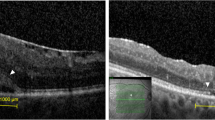

None of the patients had IRDs preoperatively. All patients (100%) had IRDs after surgery at ILM-peeled area. Postoperative OCT images showed the depth IRDs went through the ganglion cell layer (GCL) without reaching IPL (Fig. 5 A–C).

Pre- and postoperative months 1, 3, 6, and 12 (1 M, 3 M, 6 M, 12 M) optical coherence tomography (OCT) images. The depths of inner retinal dimples (IRDs) were shown plainly on cross-sectional images at macular foveal pit (arrows). The distribution of IRDs was showed on en-face OCT images. A Images of a 62-year-old woman with idiopathic macular hole (iMH). B Images of a 65-year-old man with idiopathic epiretinal membrane (iERM). C Images of a 47-year-old woman with myopic foveoschisis (mFS)